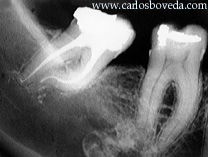

recordemos el caso:  La

paciente I. L., de sexo femenino,caucásica y

de 48 años de edad, viene referida a nuestra

consulta por su protesista luego de haber sido

atendida de emergencia en su consulta por presentar

una pulpitis en el tercer molar inferior derecho.

Al momento de la emergencia le realizaron en ese

tercer molar una eliminación de caries y

pulpotomía. Este procedimiento fue realizado

4 días antes de la consulta con nosotros. A

partir de ese momento la paciente presentó

un alivio importante de su molestia y se nos

presenta asintomática con la siguiente

imagen radiográfica :